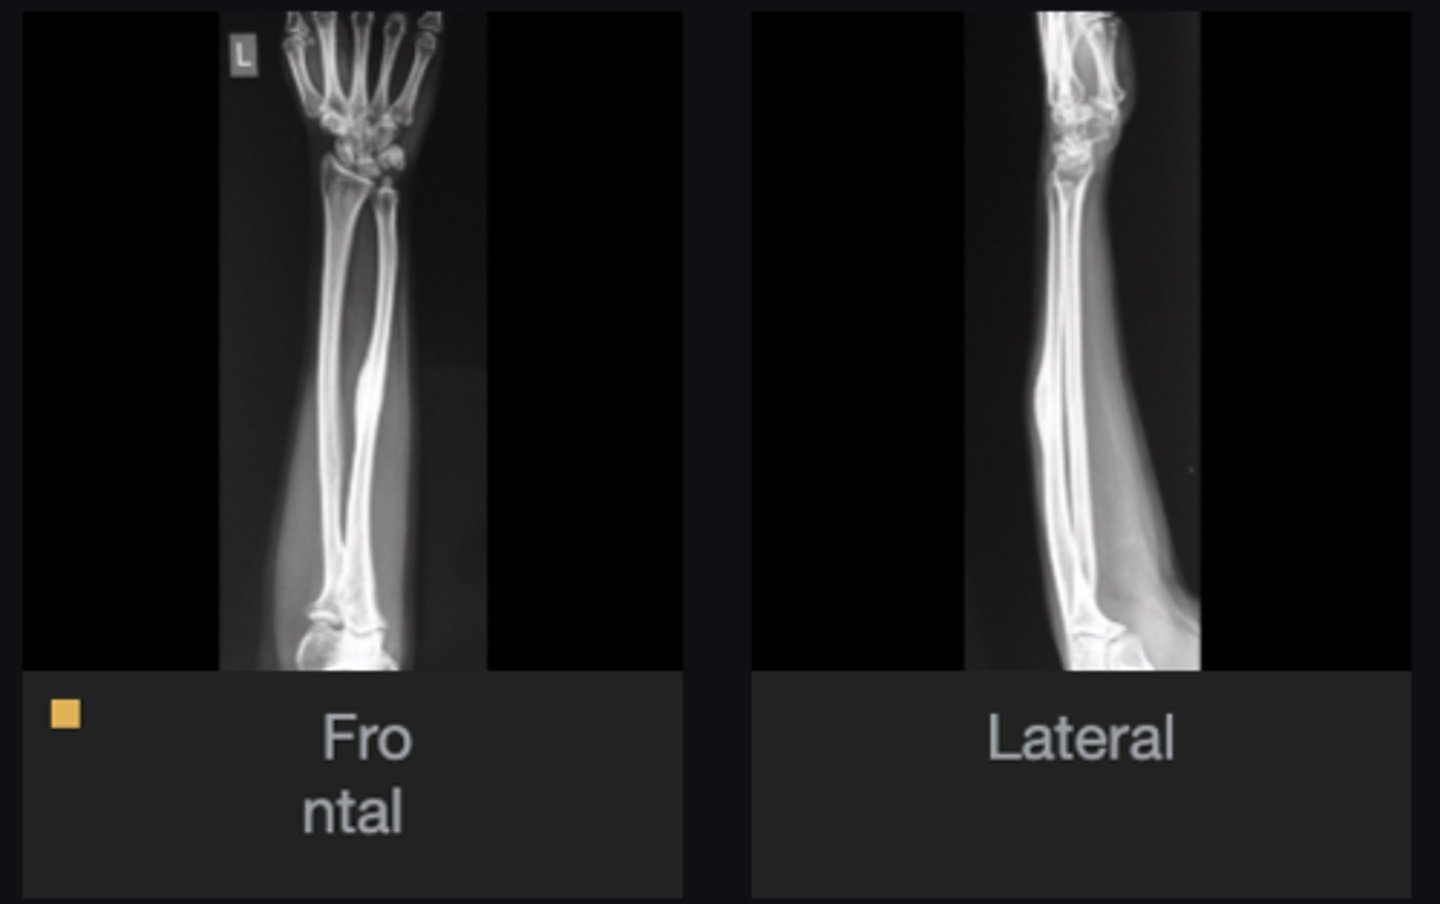

- Ulna

- Diaphysis

- Sclerotic

- Small, lucent nidus (< 1cm) in the cortex

- Geographic)

- Cortical thickening

Describe the lesion

<p>Describe the lesion</p>

Osteoid osteoma

Most likely diagnosis?

<p>Most likely diagnosis?</p>

Severe pain (worse at night, relieved by aspirin)

What is the hallmark history of a patient with this lesion?

<p>What is the hallmark history of a patient with this lesion?</p>

- Refer to orthopedist

- Adjust spine

Next step?

<p>Next step?</p>

None

Concerns/complications?

<p>Concerns/complications?</p>